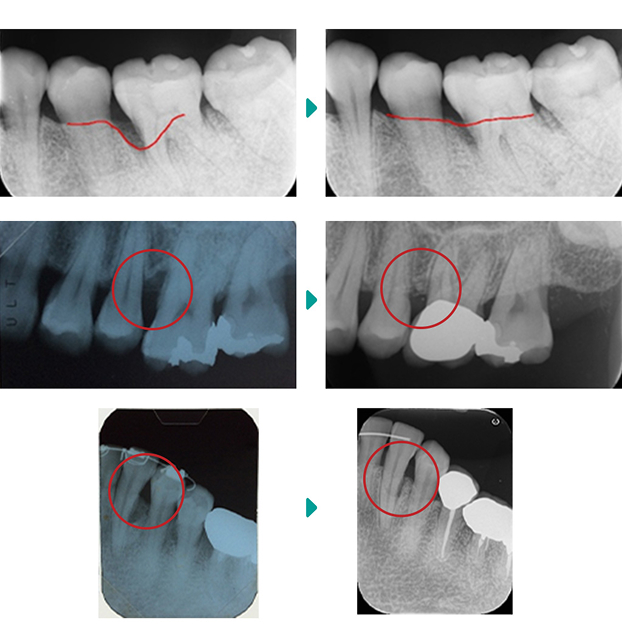

CASE OF PERIODONTAL DISEASE

当院では、様々な歯周病の患者様の治療を行ってまいりました。下記に治療事例の一部をご紹介いたします。

歯周病に関するお悩みや疑問点がありましたら、お気軽にご相談ください。なるべく早めの治療をおすすめします。

下の前歯の裏側に歯石が大量についていましたが、歯石を除去してブラッシング指導をした後、歯ぐきが改善しました。

歯茎が腫れて痛みもあり、歯周病が中程度に進行していました。簡単な歯周外科処置をすることによって歯ぐきの腫れが改善して健康な状態に戻りました。

重度の歯周病の状態で歯茎も腫れて動いている歯もありましたので、全体的に歯周外科処置を行いました。歯周病の改善がみられます。